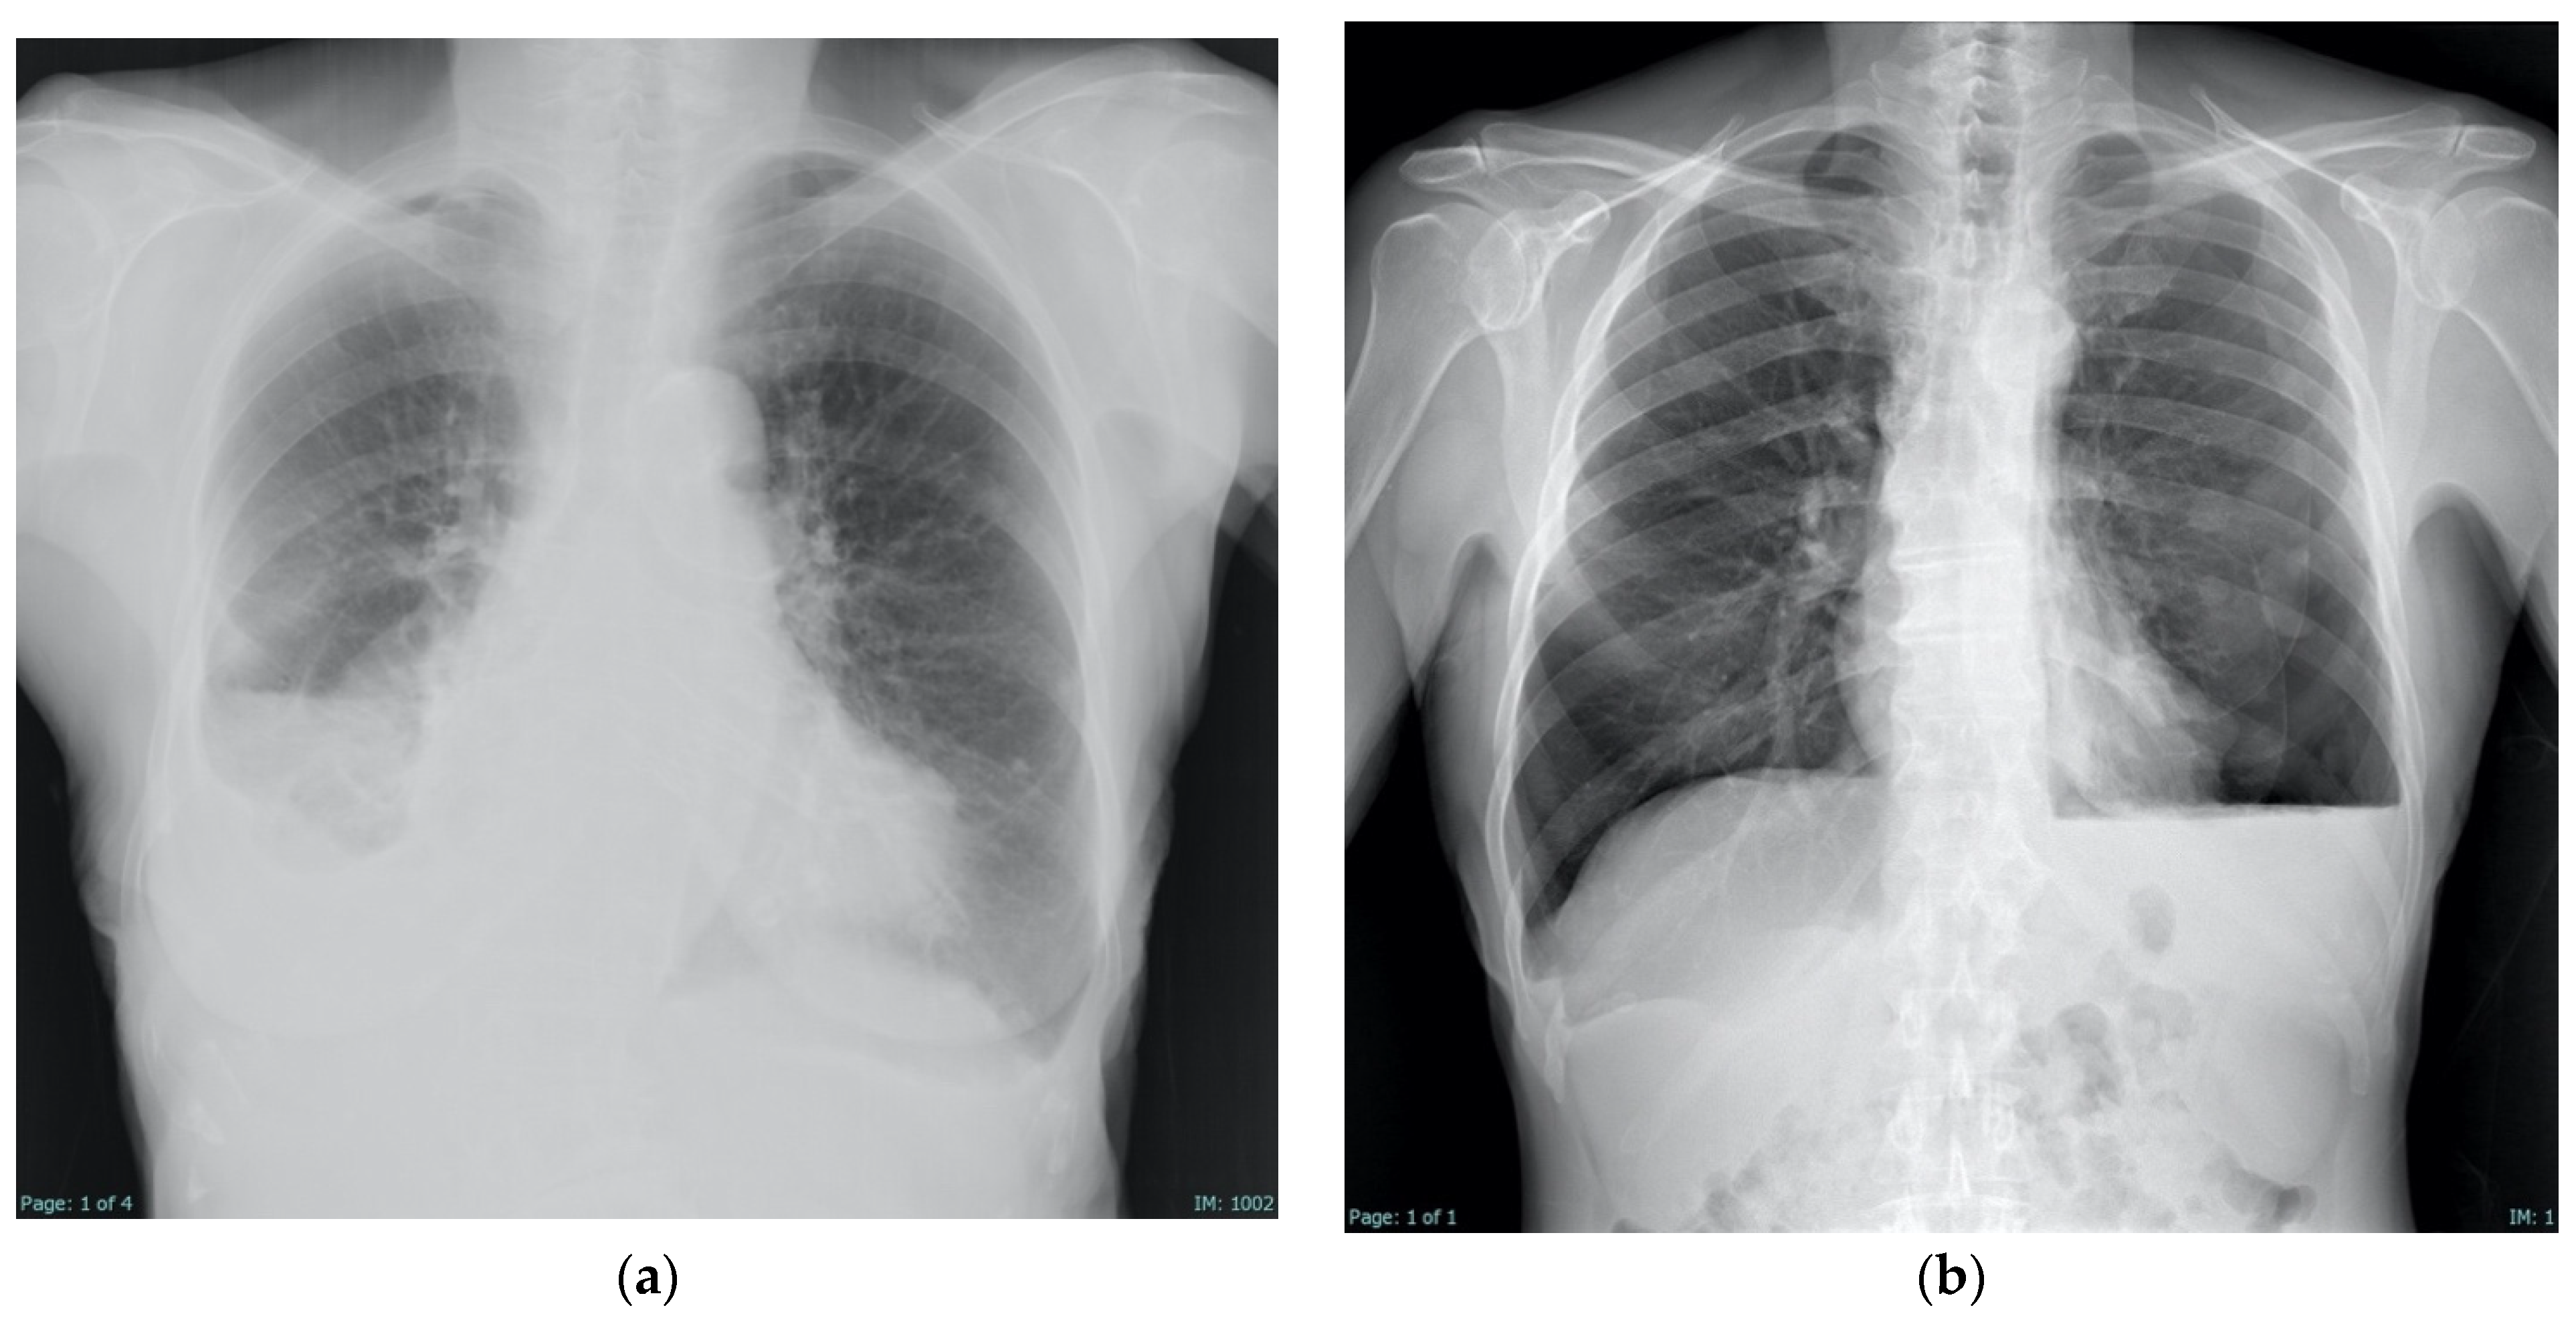

4.3. Radiologic Findings

- Martin, G.A.; Kidd, A.C.; Tsim, S.; Halford, P.; Bibby, A.; Maskell, N.A.; Blyth, K.G. Inter-Observer Variation in Image Interpretation and the Prognostic Importance of Non-Expansile Lung in Malignant Pleural Effusion. Respirology 2020, 25, 298–304. [Google Scholar] [CrossRef]